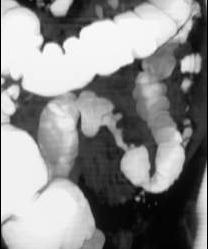

男,55岁,左下腹胀痛、并可触及包块,结合图像,应诊断为 ( )A、肠结核B、慢性溃疡性结肠炎C、结肠癌D、结肠腺瘤E、结肠crohn病

问题 男,55岁,左下腹胀痛、并可触及包块,结合图像,应诊断为 ( )

选项 A、肠结核 B、慢性溃疡性结肠炎 C、结肠癌 D、结肠腺瘤 E、结肠crohn病

答案 C